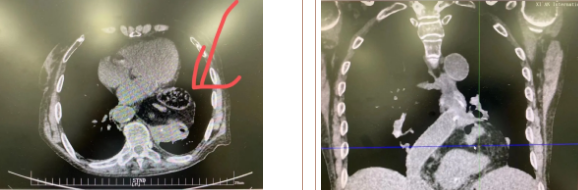

經(jīng)過三周充分準(zhǔn)備、院內(nèi)多學(xué)科會診及嚴(yán)謹(jǐn)?shù)男g(shù)前討論,西安國際醫(yī)學(xué)中心醫(yī)院胸科醫(yī)院李文海副院長帶領(lǐng)團(tuán)隊(duì)為一位82歲高齡,多臟器功能不全且合并腫瘤患者成功實(shí)施“巨大膈疝修補(bǔ) 抗返流手術(shù)”。

據(jù)了解,患者多年來進(jìn)食后出現(xiàn)惡心、嘔吐,卻未到醫(yī)院進(jìn)行檢查。3個月前患者突然出現(xiàn)無尿,全身腫脹等情況才前往就醫(yī),卻遭多家醫(yī)院拒收,輾轉(zhuǎn)來到我院就診。檢查發(fā)現(xiàn)患者已患宮頸癌、進(jìn)而引起腎后性腎衰、同時合并膈疝、出現(xiàn)泌尿道感染,病情及其復(fù)雜。

經(jīng)泌尿外科積極救治,患者腎衰癥狀緩解,隨后轉(zhuǎn)入放射治療中心進(jìn)行宮頸癌根治性放療。放療期間,患者惡心、嘔吐癥狀逐漸加重,后期無法進(jìn)食,排除機(jī)械性腸梗阻和放療因素,考慮因長期膈疝加重引起,經(jīng)胸外科會診后轉(zhuǎn)入胸外科一病區(qū)準(zhǔn)備手術(shù)治療。

麻醉手術(shù)中心副主任丁倩為減輕患者術(shù)后不適,實(shí)施單腔聯(lián)合支氣管封堵插管,同時進(jìn)行了肋間神經(jīng)阻滯麻醉。術(shù)中發(fā)現(xiàn)患者膈疝巨大,食管和疝囊分界不清,部分胃組織和結(jié)腸疝已進(jìn)入胸腔。李文海憑借豐富的臨床經(jīng)驗(yàn),仔細(xì)辨別解剖變異,有序完成分離、縫合、修補(bǔ)等一系列操作,胸外科穆強(qiáng)副主任醫(yī)師、劉歡住院醫(yī)師、麻醉手術(shù)中心團(tuán)隊(duì)通力配合,手術(shù)最終順利完成,患者安全返回胸外科監(jiān)護(hù)室病房。目前患者術(shù)后恢復(fù)良好,于近日準(zhǔn)備出院。